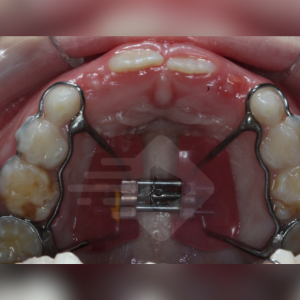

No arco inferior podemos definir que a borda Walla limita a amplitude transversal mandibular, sendo que esta pode ser identificada através da junção entre a mucosa ceratinizada e a mucosa alveolar. Observe a flecha vermelha na imagem ao lado.

Observe na imagem abaixo a borda Walla e a relação “tampa-caixa” do arco inferior e superior. Conseguiram identificar a atresia da maxila? Conseguem identificar a inclinação dos dentes inferiores para a lingual?

Na imagem ao lado conseguimos ver uma relação transversal adequada entre o arco superior e inferior, é possível ver a diferença?